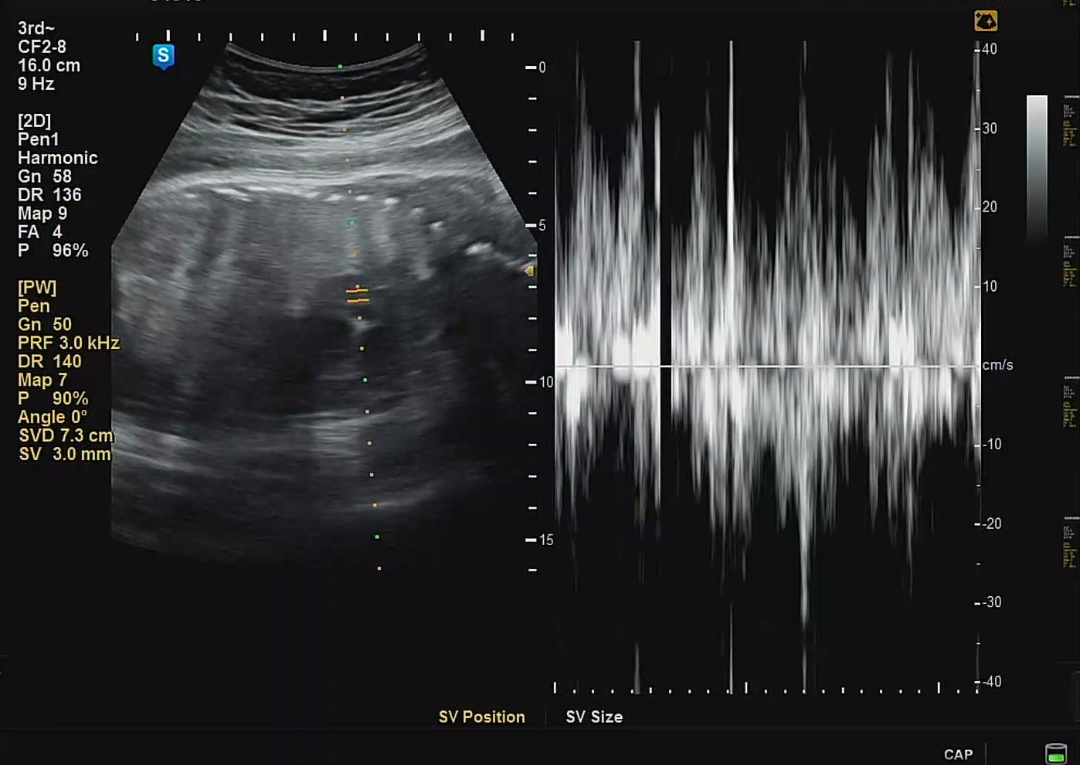

심박수와 탯줄 혈액 이동도 원활하게 잘 이동하고 있다고 한다. 우리는 제왕절개 분만을 진행할 것이기 때문에, 어느덧 2주정도 남았다. 후아 떨린다. 우리 까꿍이 만날 생각에 두근두근. 제발 건강하게 잘 나와야 할 텐데.. 걱정 걱정